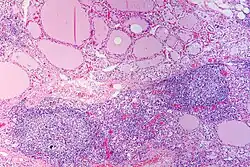

Endgültige Sicherheit bringt die histologische (feingeweblich-mikroskopische) Untersuchung von Schilddrüsengewebe, das mittels einer Feinnadelpunktion gewonnen wurde. Bei der Hashimoto-Thyreoiditis erkennt man neben anderen Kriterien vor allem ein dichtes Infiltrat von Lymphozyten und auch Lymphfollikel (siehe Abbildung), die Ausdruck der entzündlichen Vorgänge sind.